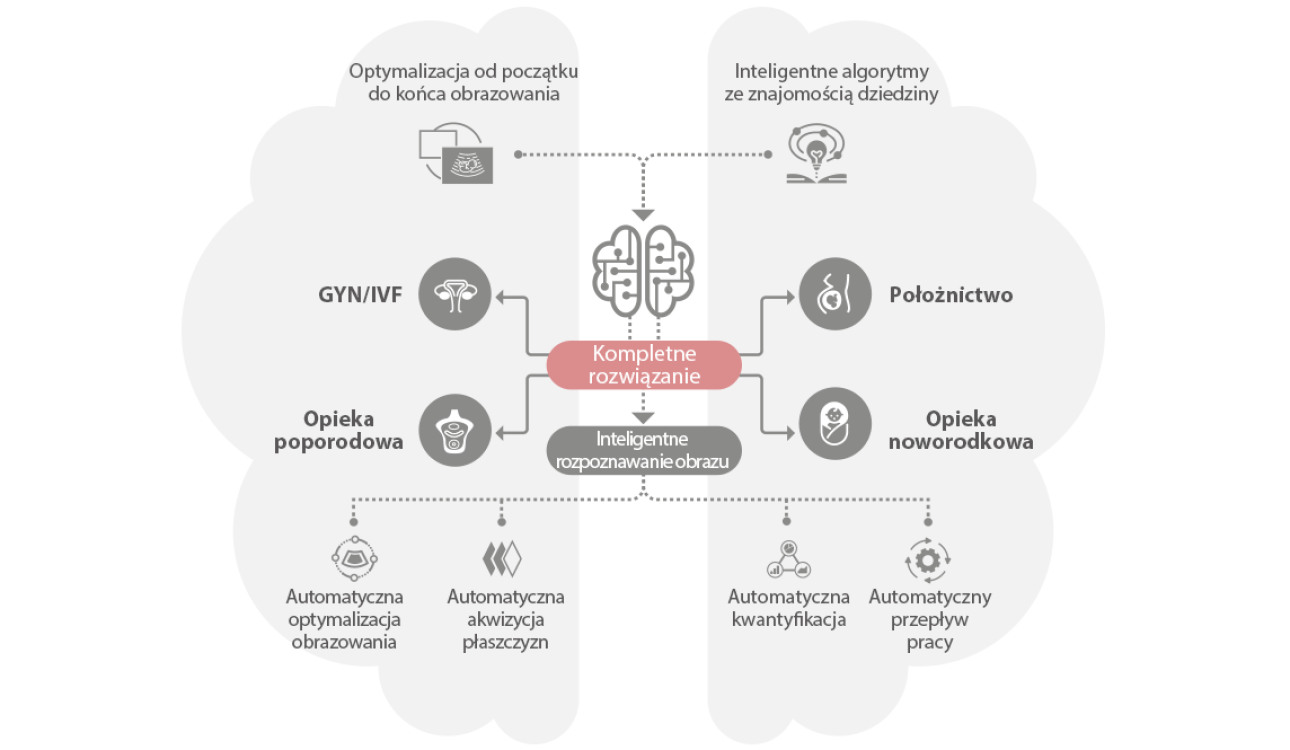

Ultrasonograf Nuewa I9 , zosta? zaprojektowany z my?l? o opiece zdrowotnej kobiet i noworodk├│w. Rozwi?zania zastosowane w Nuewa I9 zosta?y opracowane w oparciu o dog??bn? analiz? r├│?norodnych potrzeb klinicznych, aby zapewni? dok?adn? i szybk? diagnostyk?, a tak?e wyj?tkow? wydajno?? i niezwyk?? wygod? u?ytkowania.